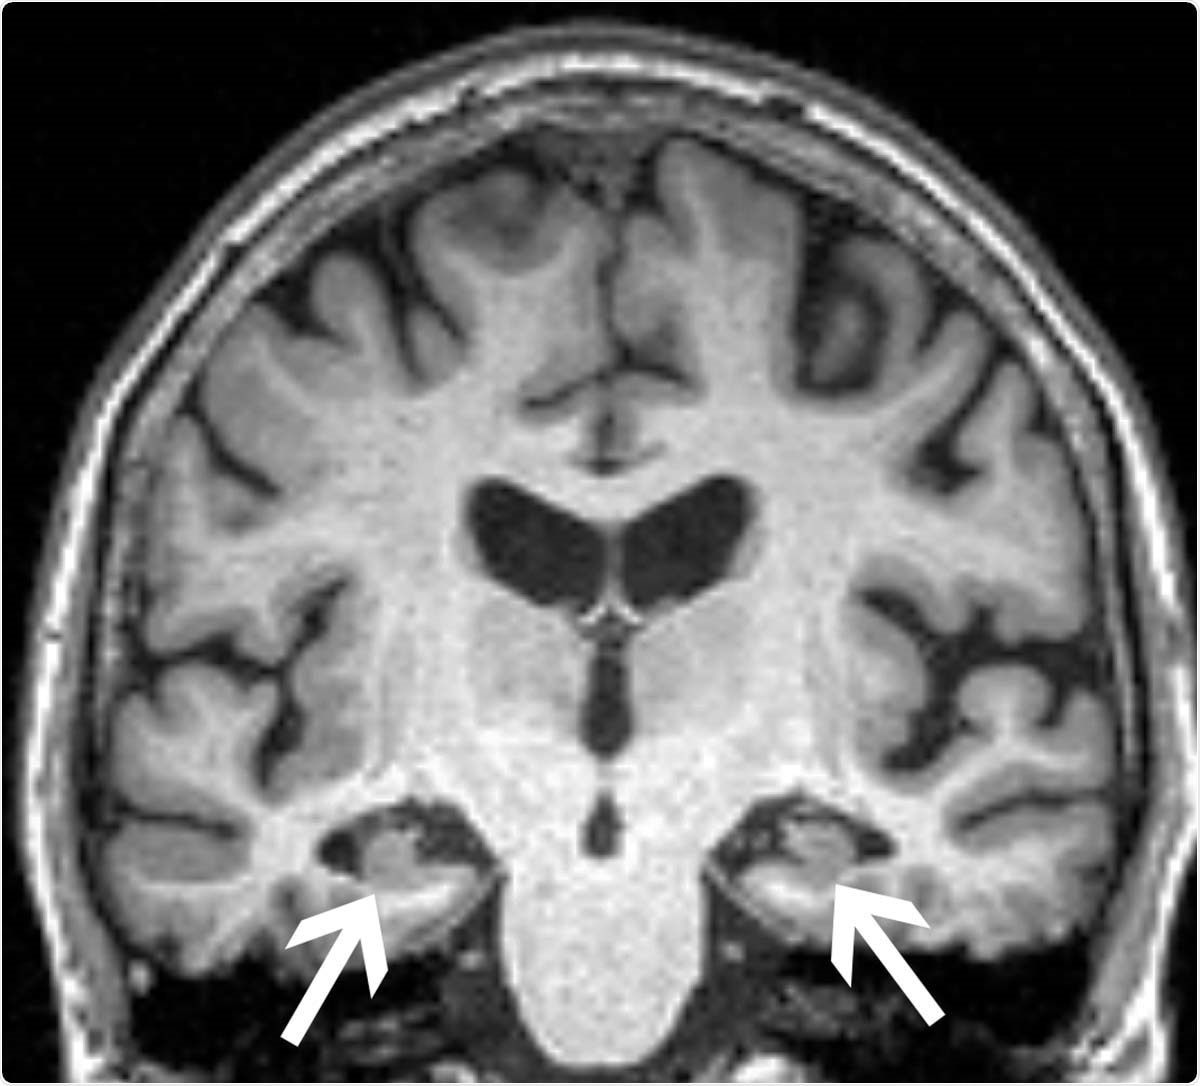

Brain MRI of a 72-year-old woman shows loss of volume of the hippocampus (arrows). The patient had all three characteristics, volume loss of the hippocampi, APOE4, and anxiety, found in the study to be associated with progression from mild cognitive impairment to dementia.

Image Credit: Radiological Society of North America

MRIs of the patients’ brains were analyzed to establish the baseline volumes of two key areas implicated in memory formation, the hippocampus, and the entorhinal cortex. The researchers also determined whether patients had the ApoE4 allele, known to be the most prevalent genetic risk factor for Alzheimer's disease. Additionally, the researchers used clinical surveys to measure anxiety.

The results showed that patients who went on to obtain a diagnosis of Alzheimer's disease were those who had significantly lower hippocampal volumes at the onset of the study. They also had reduced volumes of the entorhinal cortex and were more likely to have the ApoE4 allele. These findings were expected.